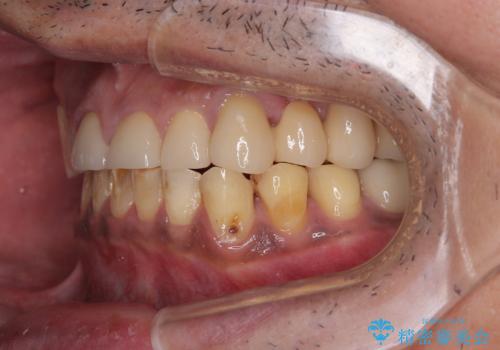

反対咬合ですり減った前歯とむし歯だらけの奥歯 総合歯科治療

- すり減った前歯や奥歯の銀歯を気にして来院された患者様です。

骨格的な反対咬合により上顎前歯の先端が顕著にすり減っている状態でした。

奥歯の欠損が散見されており、銀歯の装着されている歯も多いため、ワイヤー矯正にて歯列を調整し、その後オールセラミッククラウンにて補綴治療を行うこととしました。